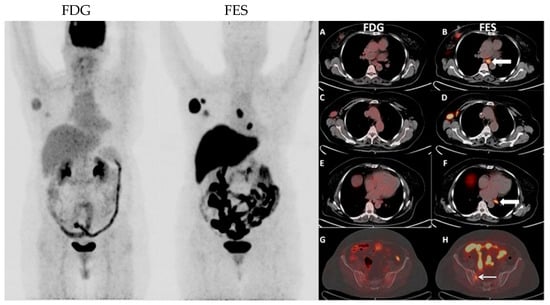

- Elboga, U.; Sahin, E.; Kus, T.; Cayirli, Y.B.; Aktas, G.; Uzun, E.; Cinkir, H.Y.; Teker, F.; Sever, O.N.; Aytekin, A.; et al. Superiority of 68Ga-FAPI PET/CT scan in detecting additional lesions compared to 18FDG PET/CT scan in breast cancer. Ann. Nucl. Med. 2021, 35, 1321–1331. [Google Scholar] [CrossRef]

- Chen, H.; Pang, Y.; Wu, J.; Zhao, L.; Hao, B.; Wu, J.; Wei, J.; Wu, S.; Zhao, L.; Luo, Z.; et al. Comparison of [(68)Ga]Ga-DOTA-FAPI-04 and [(18)F] FDG PET/CT for the diagnosis of primary and metastatic lesions in patients with various types of cancer. Eur. J. Nucl. Med. Mol. Imaging 2020, 47, 1820–1832. [Google Scholar] [CrossRef]

- Giesel, F.L.; Kratochwil, C.; Schlittenhardt, J.; Dendl, K.; Eiber, M.; Staudinger, F.; Kessler, L.; Fendler, W.P.; Lindner, T.; Koerber, S.A.; et al. Head-to-head intra-individual comparison of biodistribution and tumor uptake of (68)Ga-FAPI and (18)F-FDG PET/CT in cancer patients. Eur. J. Nucl. Med. Mol. Imaging 2021, 48, 4377–4385. [Google Scholar] [CrossRef] [PubMed]